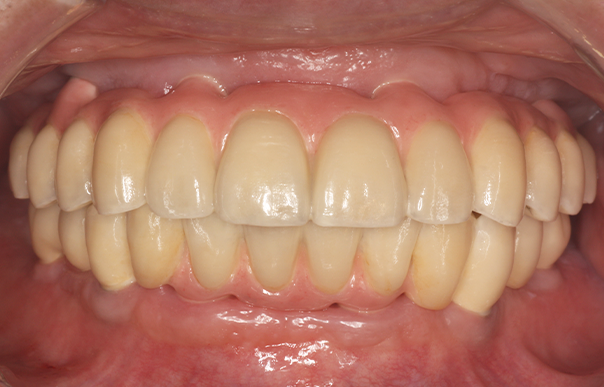

旅行や食事を楽しめるように歯を治したい 【オールオン4・オールオン6】